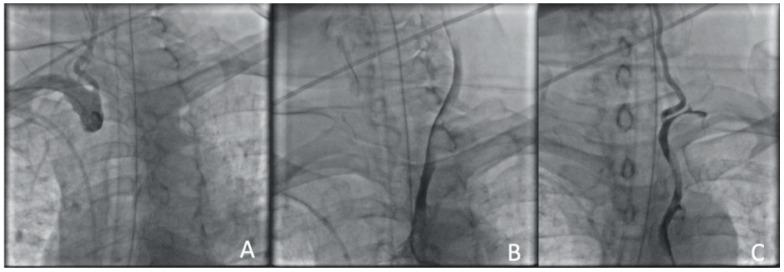

A type A aortic dissection (TAAD) is a dangerous condition requiring emergency surgery. Due to the similarity of the symptoms of cerebral malperfusion in TAAD and the signs of ischemic stroke, a differential diagnosis of these diseases is not always available. Patients with TAAD after cerebral malperfusion can have a neurological deficit. Thrombolysis is performed in this case. It can worsen the patient's condition and increase the risk of mortality and disability. The aim of the study is to evaluate the new approach to restoring cerebral perfusion during aortic dissection. This approach includes endovascular recanalization and carotid stenting.

Two clinical cases of TAAD complicated by cerebral malperfusion are described. The first patient is 73 years old and was admitted as planned to perform transcatheter aortic valve implantation (TAVI) for grade III aortic stenosis. The patient underwent transcatheter aortic valve implantation (TAVI) on the second day after admission. The second patient is 60 years old and was hospitalized by an ambulance with strong hypertension and ischemia. The surgical correction of aortic dissection was postponed until the neurological status assessment in both patients.

The surgery to correct the aorta dissection was deemed inappropriate. The carotid arteries have been reanalyzed, and cerebral perfusion has been restored in a short time in both patients.

Acute bilateral internal carotid occlusion is a potentially fatal TAAD outcome. Emergency endovascular recanalization and carotid stenting may be considered one of the few ways to restore cerebral perfusion.